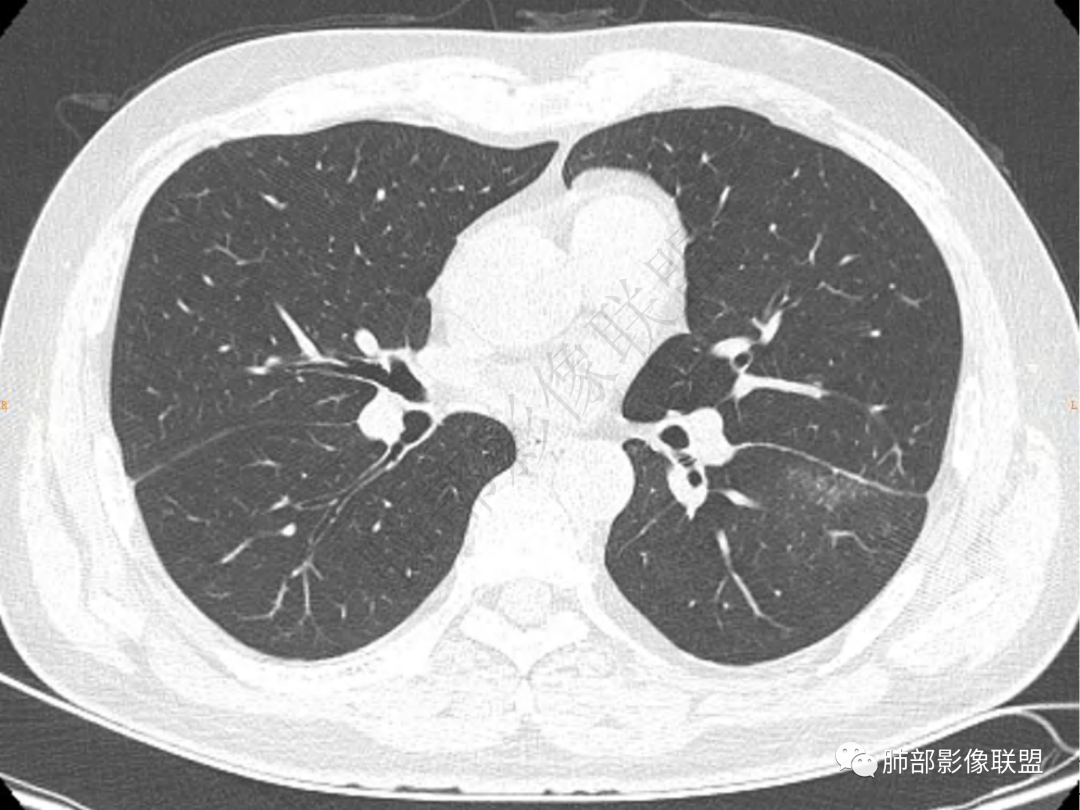

4.实性部分不均匀环形强化并显示一小范围低密度坏死区或空洞。较之肺窗,整体纵隔窗范围较小,提示病灶并不十分密实。抑或为不同时段图像。

1.病灶不够密实,没有典型分叶,收缩乏力等,支气管未见截断等,缺乏一般肿瘤性肿块特征。

2.周围磨玻璃影边界不清缺乏限制,甚至“激惹”到相邻肺叶,也许提示较明显的炎性水肿。

正如多数老师分析到的,本例病灶炎性特点比较明显。